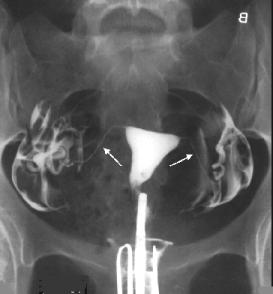

Tüpler tıkalı: Uterus normalolrak dolmuş. Her iki tüp ilaç ile dolmuş ancak uç kısımlarında genişleme mevcut. İlaç karın boşluğuna yayılmamış. Her iki tüpün uç tarafları tıkalı